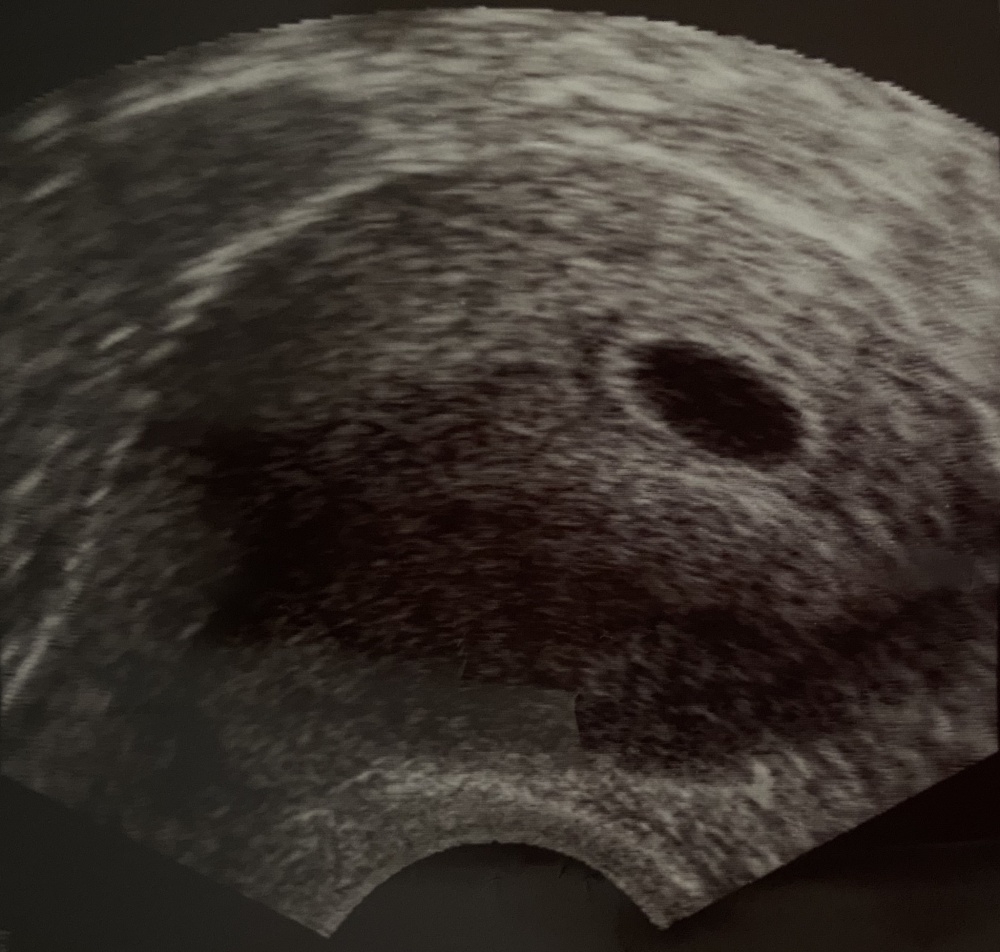

6 Ssw Nichts Auf Ultraschall Zu Sehen. Außerdem kann durch die zusätzliche dopplersonographie. Zwischen der 11+0 und 13+6 ssw wird ein früher fehlbildungsultraschall durchgeführt.

Zwischen Der 11+0 Und 13+6 Ssw Wird Ein Früher Fehlbildungsultraschall Durchgeführt.

Das liegt nicht daran, dass die schwangere jetzt “für zwei essen” muss, sondern am hormonhaushalt, der kräftig durcheinandergewürfelt wird, um dem neuen bauchbewohner ein sicheres und gutes umfeld. Bestimmte messwerte des ultraschalls werden in kombination mit der bestimmung der blutwerte papp a und hcg und anderen faktoren zu einer risikoberechnung für das vorliegen einer trisomie 13, 18 und 21 kombiniert. Bonifatius hospitalgesellschaft lingen, der als freigemeinnütziger kirchlicher träger vier allgemeinkrankenhäuser sowie verschiedene ambulante und stationäre einrichtungen der altenpflege und altenhilfe betreibt.

Außerdem Kann Durch Die Zusätzliche Dopplersonographie.